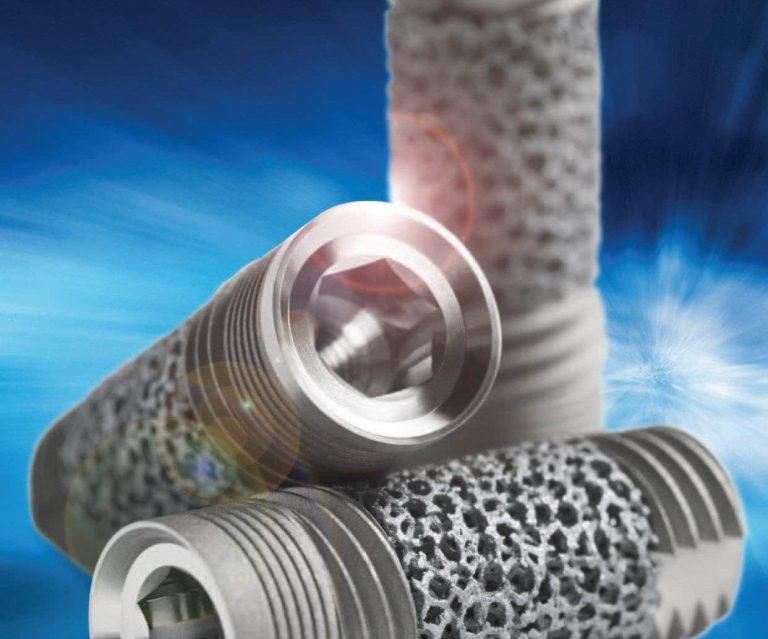

- ایمپلنت دندان: جایگزینی دندان های از دست رفته با بهترین برند های ایمپلنت.